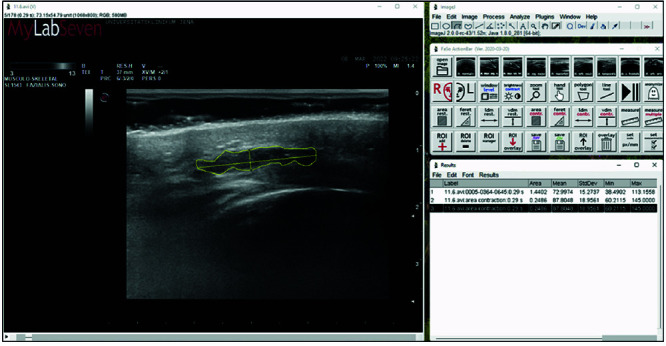

Functional Electrical Stimulation (FES) is an established intervention for a range of muscular and neurological disorders that has already been studied in numerous publications. However, its application to Peripheral Facial nerve Paralysis (PFP) still needs to be sufficiently investigated. As the first approach known to the authors, this study examines the effect of FES on the facial muscles in complete PFP using ultrasonography as a means of observation. In a prospective single-center observational pilot study, ten patients with complete PFP, confirmed by needle-electromyography (EMG), performed FES of the affected lateral mouth region at home twice daily for 20 minutes. The facial muscles' Cross-Sectional Area (CSA) was regularly assessed using sonographic quantification. While the CSA of most non-stimulated muscles decreased considerably during ongoing paralysis, a significant CSA increase of the Zygomaticus Muscle (ZYG), which was regularly subjected to FES, could be demonstrated. FES can halt the atrophy of denervated ZYG and potentially other facial muscles. Further investigations with a more significant patient collective are recommended. From now on, FES could be established as an additive method in the non-invasive treatment of PFP.